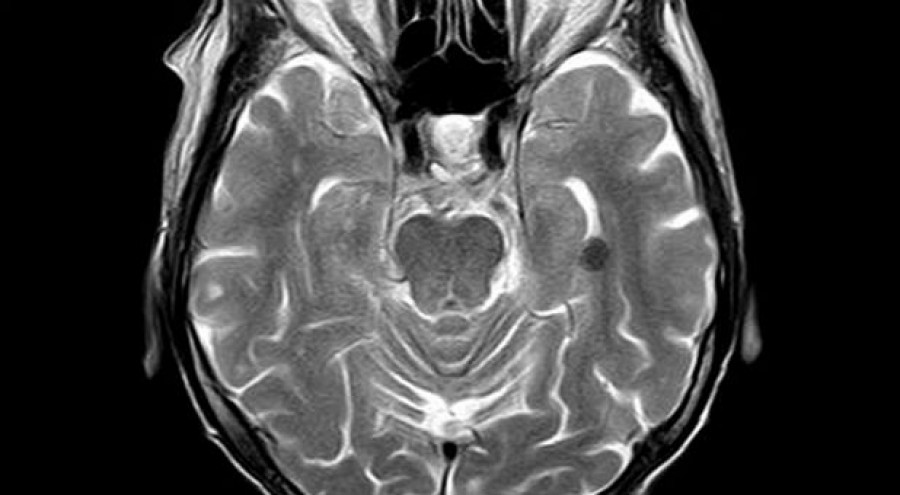

Ken Gorman suffered excruciating pain after a small lump, discovered at the end of May 2013, grew bigger and bigger. Doctors prescribed tablets for the pain and sent him to Rotherham General Hospital for investigation, where an MRI scan found three tumors (or three broken sections of a tumor) wrapped around the central nerve in the side of his face.

"After another scan, he found that the tumors had disappeared without trace, and the operation was cancelled! The surgeon and nurses were speechless when I told them how I was healed. I have been called back for an annual check-up since then, and there is no sign of any tumor. Hallelujah, thank you Jesus!"